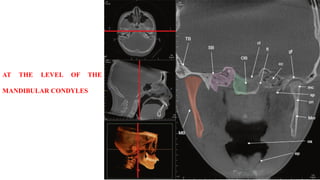

AT THE LEVEL OF THE

MANDIBULAR CONDYLES

AT THE LEVELOF THE MANDIBULAR CONDYLES

• 80.